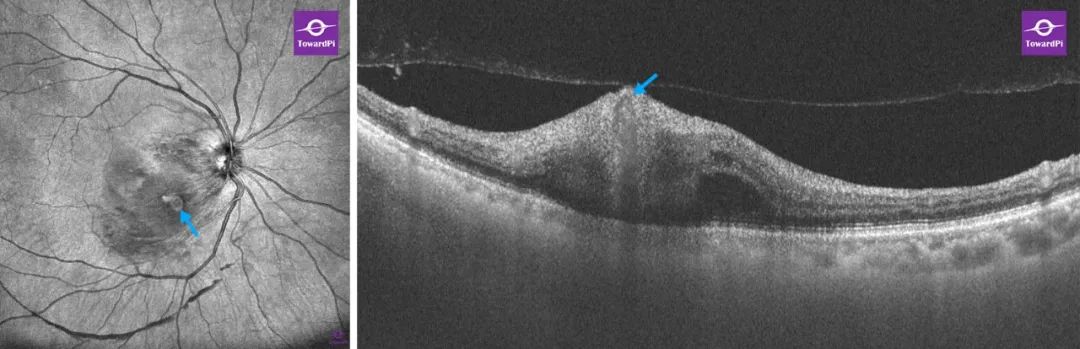

双眼屈光间质混浊,右眼位于视盘颞下方第2级动脉分支处可见蓝色圈内呈梭病形灶; 左眼视网膜未见明显异常。

图湃超广角全域扫频OCT(右眼)

OCTA(12mmX12mm扫描范围):视网膜表层血流图结合enface图可清晰的观察到动脉瘤所处位置及其形态和所累及范围,其与视网膜动脉血管吻合,在视网膜表层血流图上呈白色团状高密度血流信号,对应的断层血流OCT上可见瘤体内丰富的红色血流信号。

3D OCTA:切换至3D OCTA模式可更直观的观察到大动脉瘤体形态,及黄斑区及视盘颞下方的局部隆起。

3D-OCTA功能可帮助医生了解大动脉瘤与视网膜血管网的空间位置关系,可用于医生示教,亦方便患者对自身病情的理解。